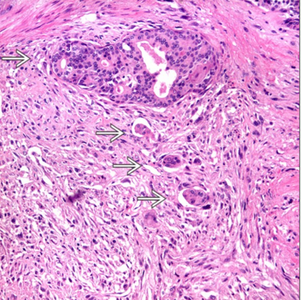

Focus of perineural invasion is noted.

● Perineural and Lymphovascular Invasion:

· Seen in 75–90% of radical prostatectomy specimens.

· Indicator of potential extra- prostatic extension, and is associated with higher Gleason score and volume.

● Extraprostatic extension: is defined by any of the features below

Presence of tumor beyond the confines of the prostate gland

Tumor extension into fat;

Tumor involving loose connective tissue in the plane of fat or beyond;

Tumor involves perineural spaces in the neurovascular bundles, even in the absence of periprostatic fat involvement

Descriptors used when reporting EPE: focal and non-focal